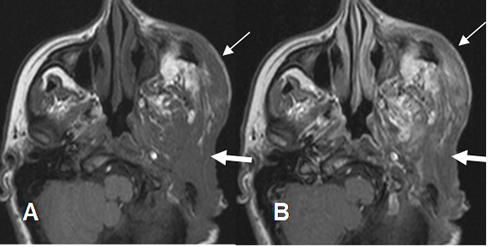

Fig 182. Neurofibroma plexiforme.

A: RM axial en T1 simple y B: RM axial en T1 con contraste. Cambios PostQx por neurofibroma plexiforme. Hay alteración en la configuración de la fosa subtemporal, región mastoidea y CAI. (Flechas gruesas). Persistencia de tejido blando sobre el arco cigomático, que realza con el contraste, por tumor residual. (Flechas delgadas).